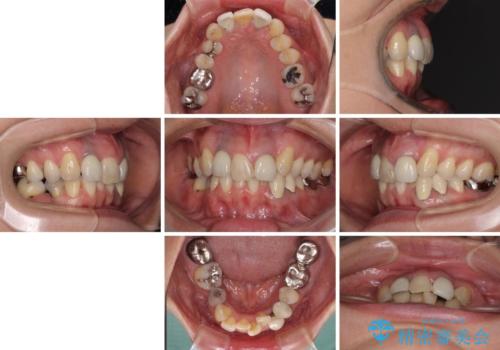

- 非対称な前歯や奥歯の目立つ銀歯を気にして来院された患者様です。

左上前から2番目の歯は、以前裏側に位置していたことから抜歯をされていましたが、前歯の非対称が長年気になっているとのことでした。

矯正治療によって前歯にスペースを作り、左右対称となるようにオールセラミッククラウンにて補綴治療を行うとしました。

他にも奥歯の咬み合わせに問題があったので、全顎的な矯正治療を行い、前歯以外にも口を開けたときに目立つ奥の銀歯をセラミッククラウンにて補綴治療を行うこととしました。